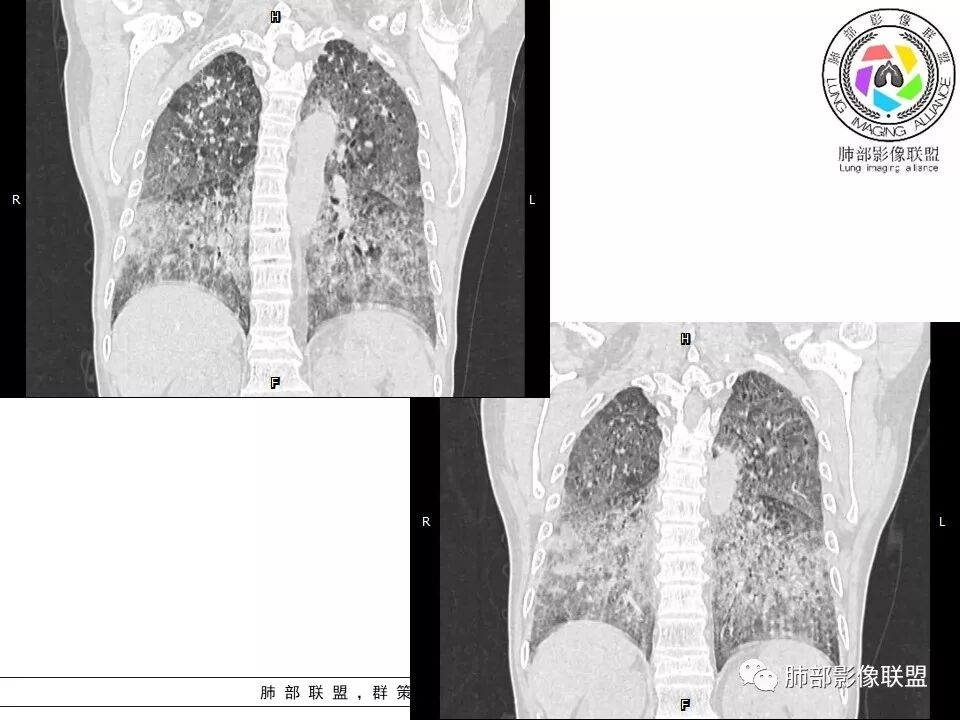

徐婕:双肺弥漫磨玻璃,铺路石,部分斑片实变。病程一年,血白细胞增高,考虑肺泡蛋白,合并双肺感染?鉴别腺癌

八爪:弥漫分布磨玻璃密度影,小叶间隔增厚,典型铺路石征,考虑PAP伴发感染性病变,鉴别特发性间质性肺炎,弥漫性腺癌,建议支气管灌洗;左肺上叶舌段不规则团片状阴影,显示不清,密切随访

笨丫头:双肺弥漫磨玻璃影,间质性改变,既往有煤炭工作史,考虑尘肺,左肺占位,边界不清,不除外合并肿瘤,腺癌?

小谢:慢性病程,无发热,双肺弥漫性病变,GGO,铺路石征,首先考虑PAP,鉴别肺腺癌

一米阳光:中老年男性,病程长。双肺弥漫性ggo,小叶间隔明显增厚,铺路石样改变,考虑PAP,鉴别pcp。建议支气管镜检查并灌洗。病史有尘肺接触史,排除尘肺合并结核

郑氏刀刀:双肺弥漫性磨玻璃影,伴铺路石征,下叶为主,且见斑片实变影,白细胞高,结合执业史,尘肺,PAP伴感染,腺癌待排。

小景:双肺弥漫磨玻璃影,小叶间隔增厚,呈碎石路征。患者粉尘接触史,考虑PAP。左肺舌段病灶,抗感染无吸收,腺癌待排。

小赵:中老年男性患者。慢性病程,多次咳黄痰,治疗效果一般,反复发生。CT表现为双肺弥漫磨玻璃样改变,并呈细网格样铺路石状改变,上下肺无明显差异。双下肺为主多发渗出实变,边界不清,抗炎治疗后病变吸收不明显,局部似有进展。考虑肺泡蛋白沉积症基础上合并感染。肿瘤标志物高,中老年患者,肺炎型肺癌不除外。

上肺为主小叶中心型肺气肿——吸烟

碎石路征,下肺为主

肺部结节

左上叶斑片状高密度影

肺血坠积